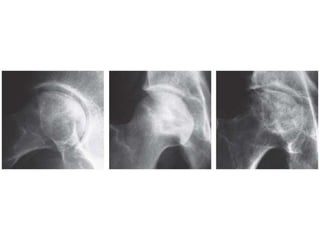

Ficat and the Steinberg Classification

Stage 1 • X-ray - no changes

• Diagnosis will be based on

intra-osseous pressure and

bone biopsy

Stage 2 Femoral head contour was

still normal but there were

early signs of Reactive

changes in the subchondral

bone

Stage 3 Clear evidence of

osteonecrosis and

structural damage and

distortion of bone

outline.

Stage 4 Collapse of articular

surface and signs of OA.

Ficat and theSteinberg Classification Stage 1 • X-ray - no changes • Diagnosis will be based on intra-osseous pressure and bone biopsy Stage 2 Femoral head contour was still normal but there were early signs of Reactive changes in the subchondral bone

• 34.

Stage 3 Clearevidence of osteonecrosis and structural damage and distortion of bone outline. Stage 4 Collapse of articular surface and signs of OA.